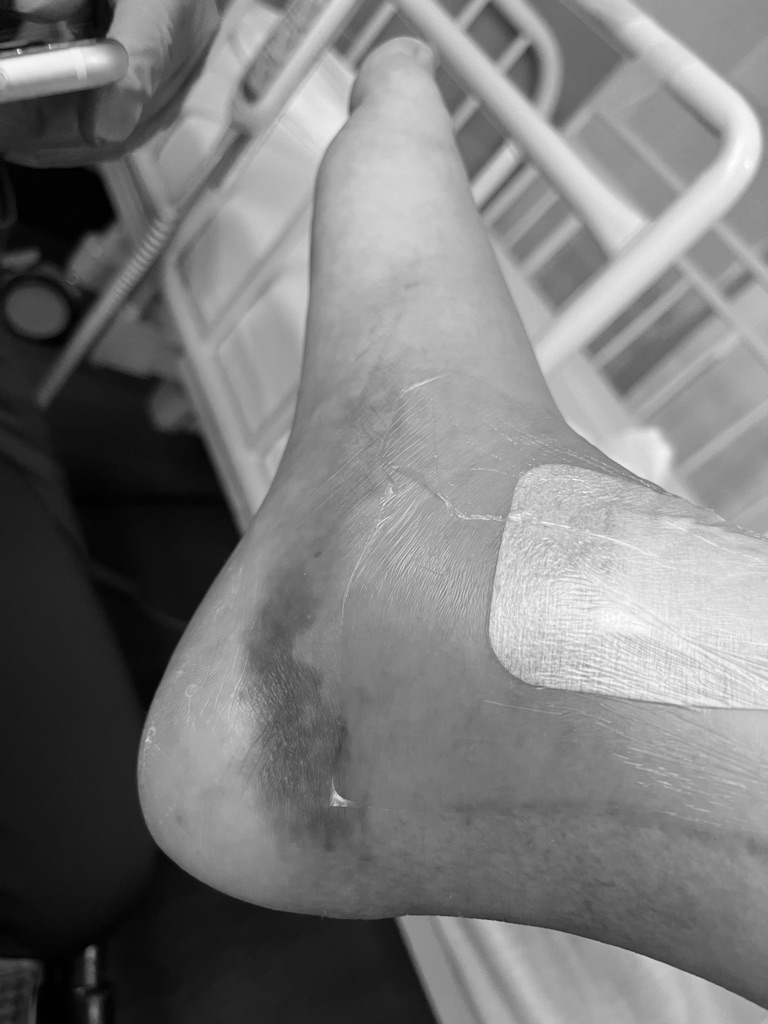

右足首、腓骨遠位端の骨折と脱臼。

退院直後から、足首全体がパンパンに腫れ上がっていた。